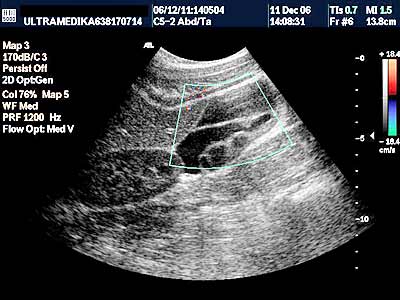

Paraovarijalne / paratubarne ciste

Paraovarijalne /

paratubarne ciste